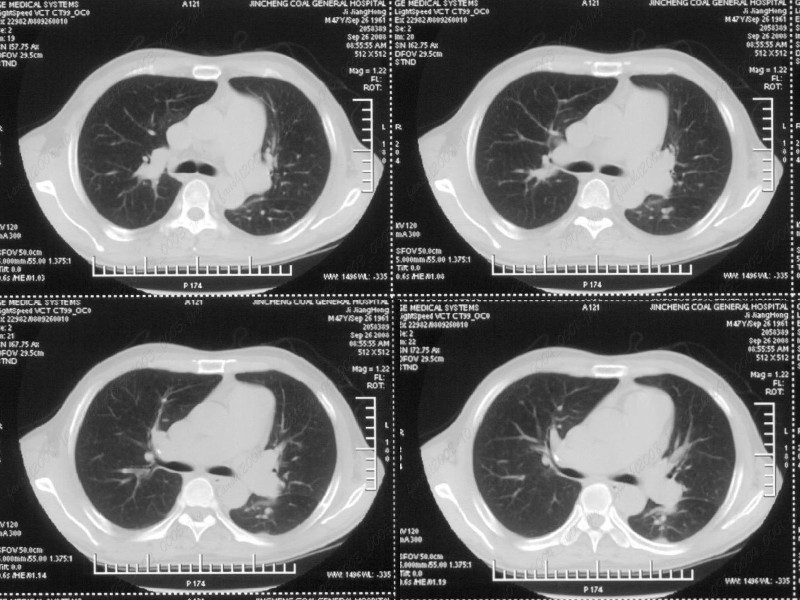

男性,47岁。胸部不适一年,ct检查发现右胸膜下结节。http://www.radida.com/bbs/forum.php?mod=viewthread&tid=46094

图像很清,资料很全。工作做的很细,向您学习!观阁下的强化图像发现,您们强化后扫描时间挺早,延迟时间大约在16—18秒之间吧。估计目的是为了观察肺动脉及分支的情况。但现有的资料并不能提示动脉栓塞改变。建议楼主可在机器上仔细观察,或许会有异常发现。另外,个人感觉右侧应为肺内结节而非胸膜结节。考虑肺内良性小结节,炎性假瘤可能性大。

病灶周围似有纤维化征像,增强明显强化,但中央可见点状低强化区,考虑慢性病变可能如炎性假瘤等,病灶边缘部分毛糙有切迹,双侧胸腔少量积液影,不除外恶性

结节未见明显强化,局部胸膜增后粘连,内缘纹理影增重伴小围星灶,局部胸膜下小三角状实变影,尖端见纤维索牵扯征,综合考虑炎性病变,有增殖表现,不出外tb灶

右肺中叶外侧段胸膜下结节状病灶,性质待定(不排除周围型肺癌可能)。

小结节的周围似乎与斜裂的走行有关,边缘分界不很清楚,与侧胸膜关系密切,有轻度强化,不能除外恶性,建议密切观察。